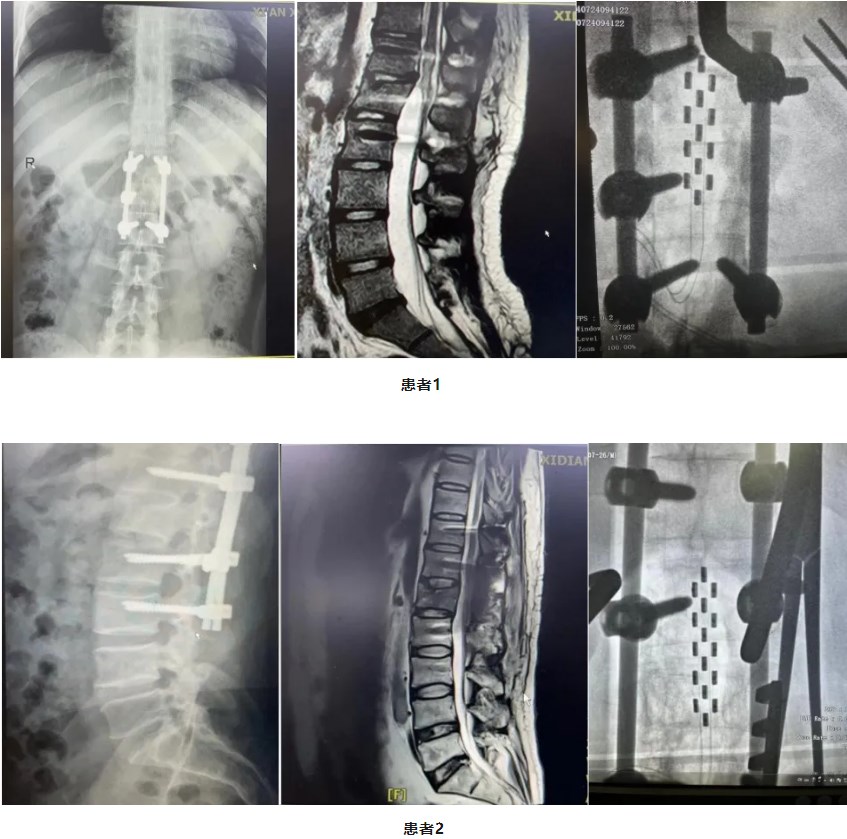

兩位來自外省的男性患者,均因腰1椎體骨折導致脊髓損傷、截癱、大小便障礙。傷后1年余,患者輾轉(zhuǎn)多家醫(yī)院行康復治療,目前雙下肢雖可扶拐站立,但仍行走困難,加之大小便障礙一直困擾,嚴重影響生活。在經(jīng)過廣泛的信息搜尋后得知西安市西電集團醫(yī)院神經(jīng)外科馮磊主任醫(yī)師開展的脊髓神經(jīng)電刺激術(shù)治療脊髓損傷導致截癱、大小便障礙方面效果顯著,遂滿懷希望前來就診,希望通過手術(shù)治療能為自己帶來“重生”!

兩位患者于7月中旬先后入院,神經(jīng)外科林濤主任組織相關(guān)科室對患者病情進行細致評估和周密的術(shù)前準備,7月24日和7月26日先后為兩位患者完成了手術(shù)。目前,患者術(shù)后恢復良好已下床適量活動,下一步準備開啟神經(jīng)刺激器,繼續(xù)為患者進行康復綜合訓練治療,促進下肢行走及大小便功能進一步康復。